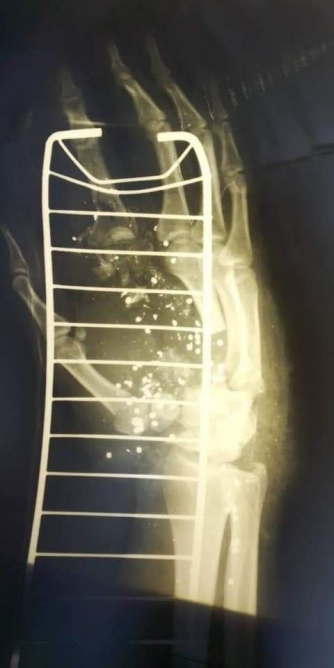

Появилось фото раненого патрульного, которого вчера подстрелил "голосеевский стрелок".

Напомним, вчера, 7 июля, в Киеве стрелок выстрелил в полицейских, которые прибыли на вызов из охотничьего ружья, а затем пытался поджечь свою квартиру в многоэтажке. Мужчину задержали. Один из полицейских был ранен в руку.

Сейчас медики собирают кости кисти руки полицейского. По словам врачей, все должно пройти без осложнений. А через полгода пальцы снова будут работать.